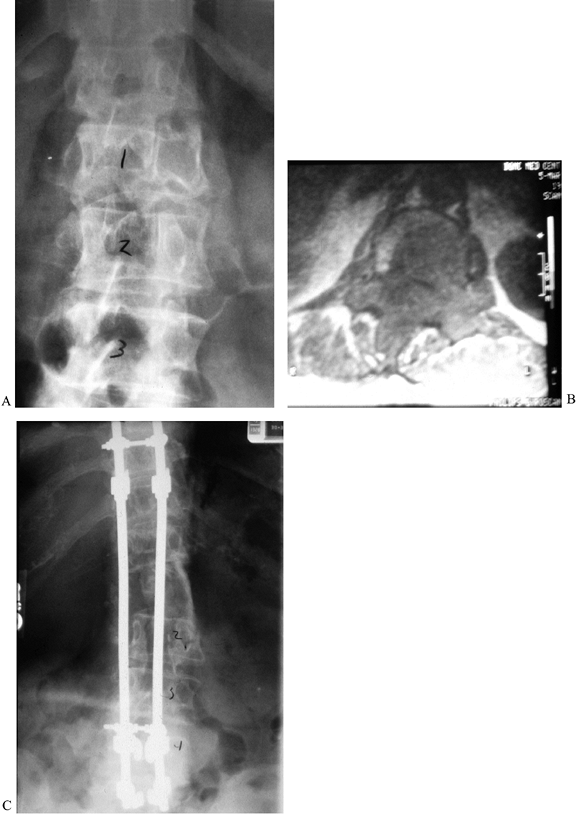

excision is the key to eradicating these tumors (Fig. 152.3). Anterior/posterior vertebrectomy with an en bloc

![]() |

|

Figure 152.3. Treatment of giant cell tumor. A: CT scan showing extensive destruction of L-1 vertebral body. B:

An aggressive approach is taken to limit the chance of local recurrence. Wide laminectomy over the tumor level allows pedicle resection and release of the posterior annulus. C: After the posterior annulus is sectioned, the dorsal instrumentation is applied to stabilize the spine. D: An anterior approach allows en bloc vertebrectomy by completing the discectomies and removing the tumor with the overlying soft tissues adherent. |